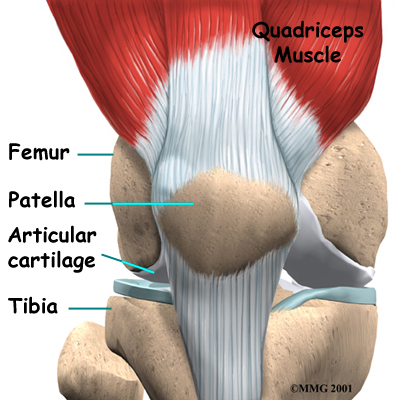

The knee joint is formed where the thighbone (femur) meets the shinbone (tibia). A smooth cushion of articular cartilage covers the end surfaces of both of these bones so that they slide against one another smoothly. The articular cartilage is kept slippery by joint fluid made by the joint lining (synovial membrane). The fluid is contained in a soft tissue enclosure around the knee joint called the joint capsule.

The patella, or kneecap, is the moveable bone on the front of the knee. It is wrapped inside a tendon that connects the large muscles on the front of the thigh, the quadriceps muscles, to the lower leg bone. The surface on the back of the patella is covered with articular cartilage. It glides within a groove on the front of the femur.